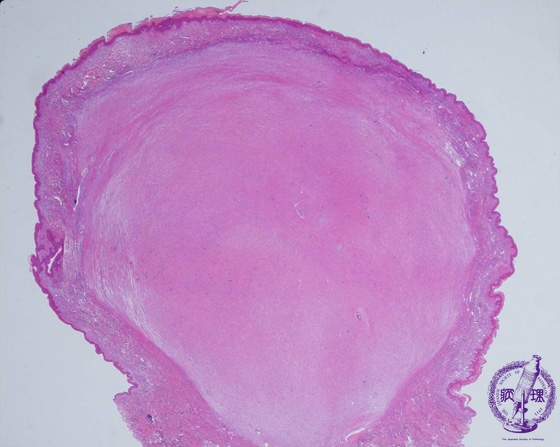

Microscopic findings: Tumor cells show diffuse proliferation. The tumor shows expansive growth and the border of the tumor is relatively clear. Sometimes skin appendages remain inside the tumor.